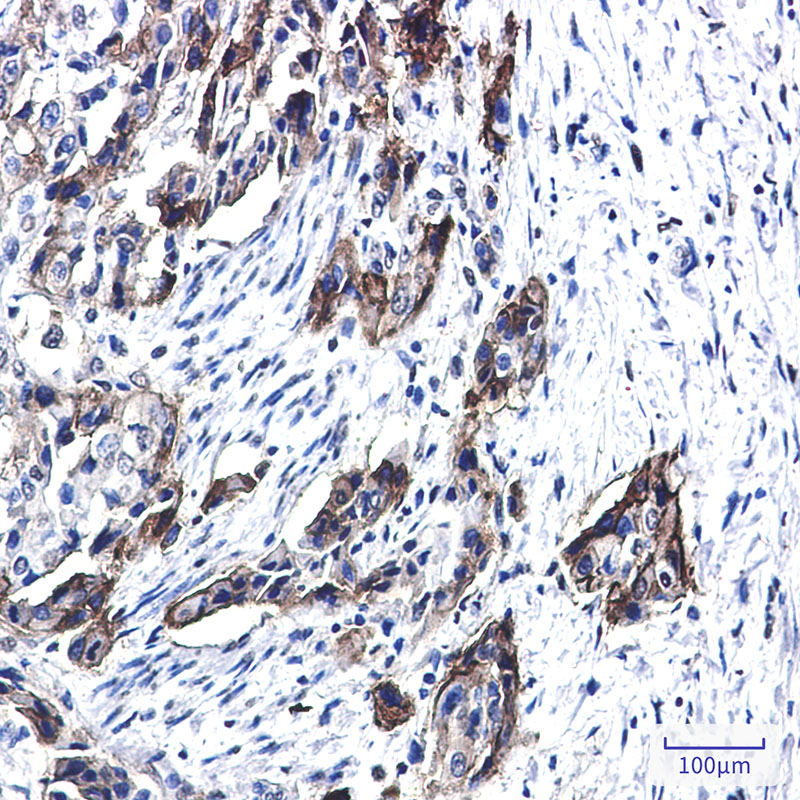

- Immunohistochemistry analysis of paraffin-embedded Human lung cancer tissue using Tissue Factor antibody. High-pressure and temperature Sodium Citrate pH 6.0 was used for antigen retrieval.